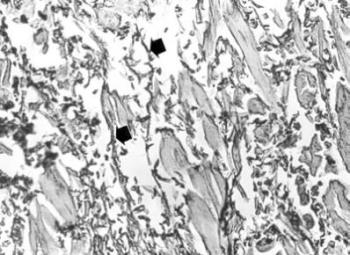

12. ábra. A 19. századi férfi múmia aortájában kifekélyesedett atheromás plakk, a koleszterin kristályok helyét tű alakú üregek (csillag) jelzik. HE festés 150× nagyítás